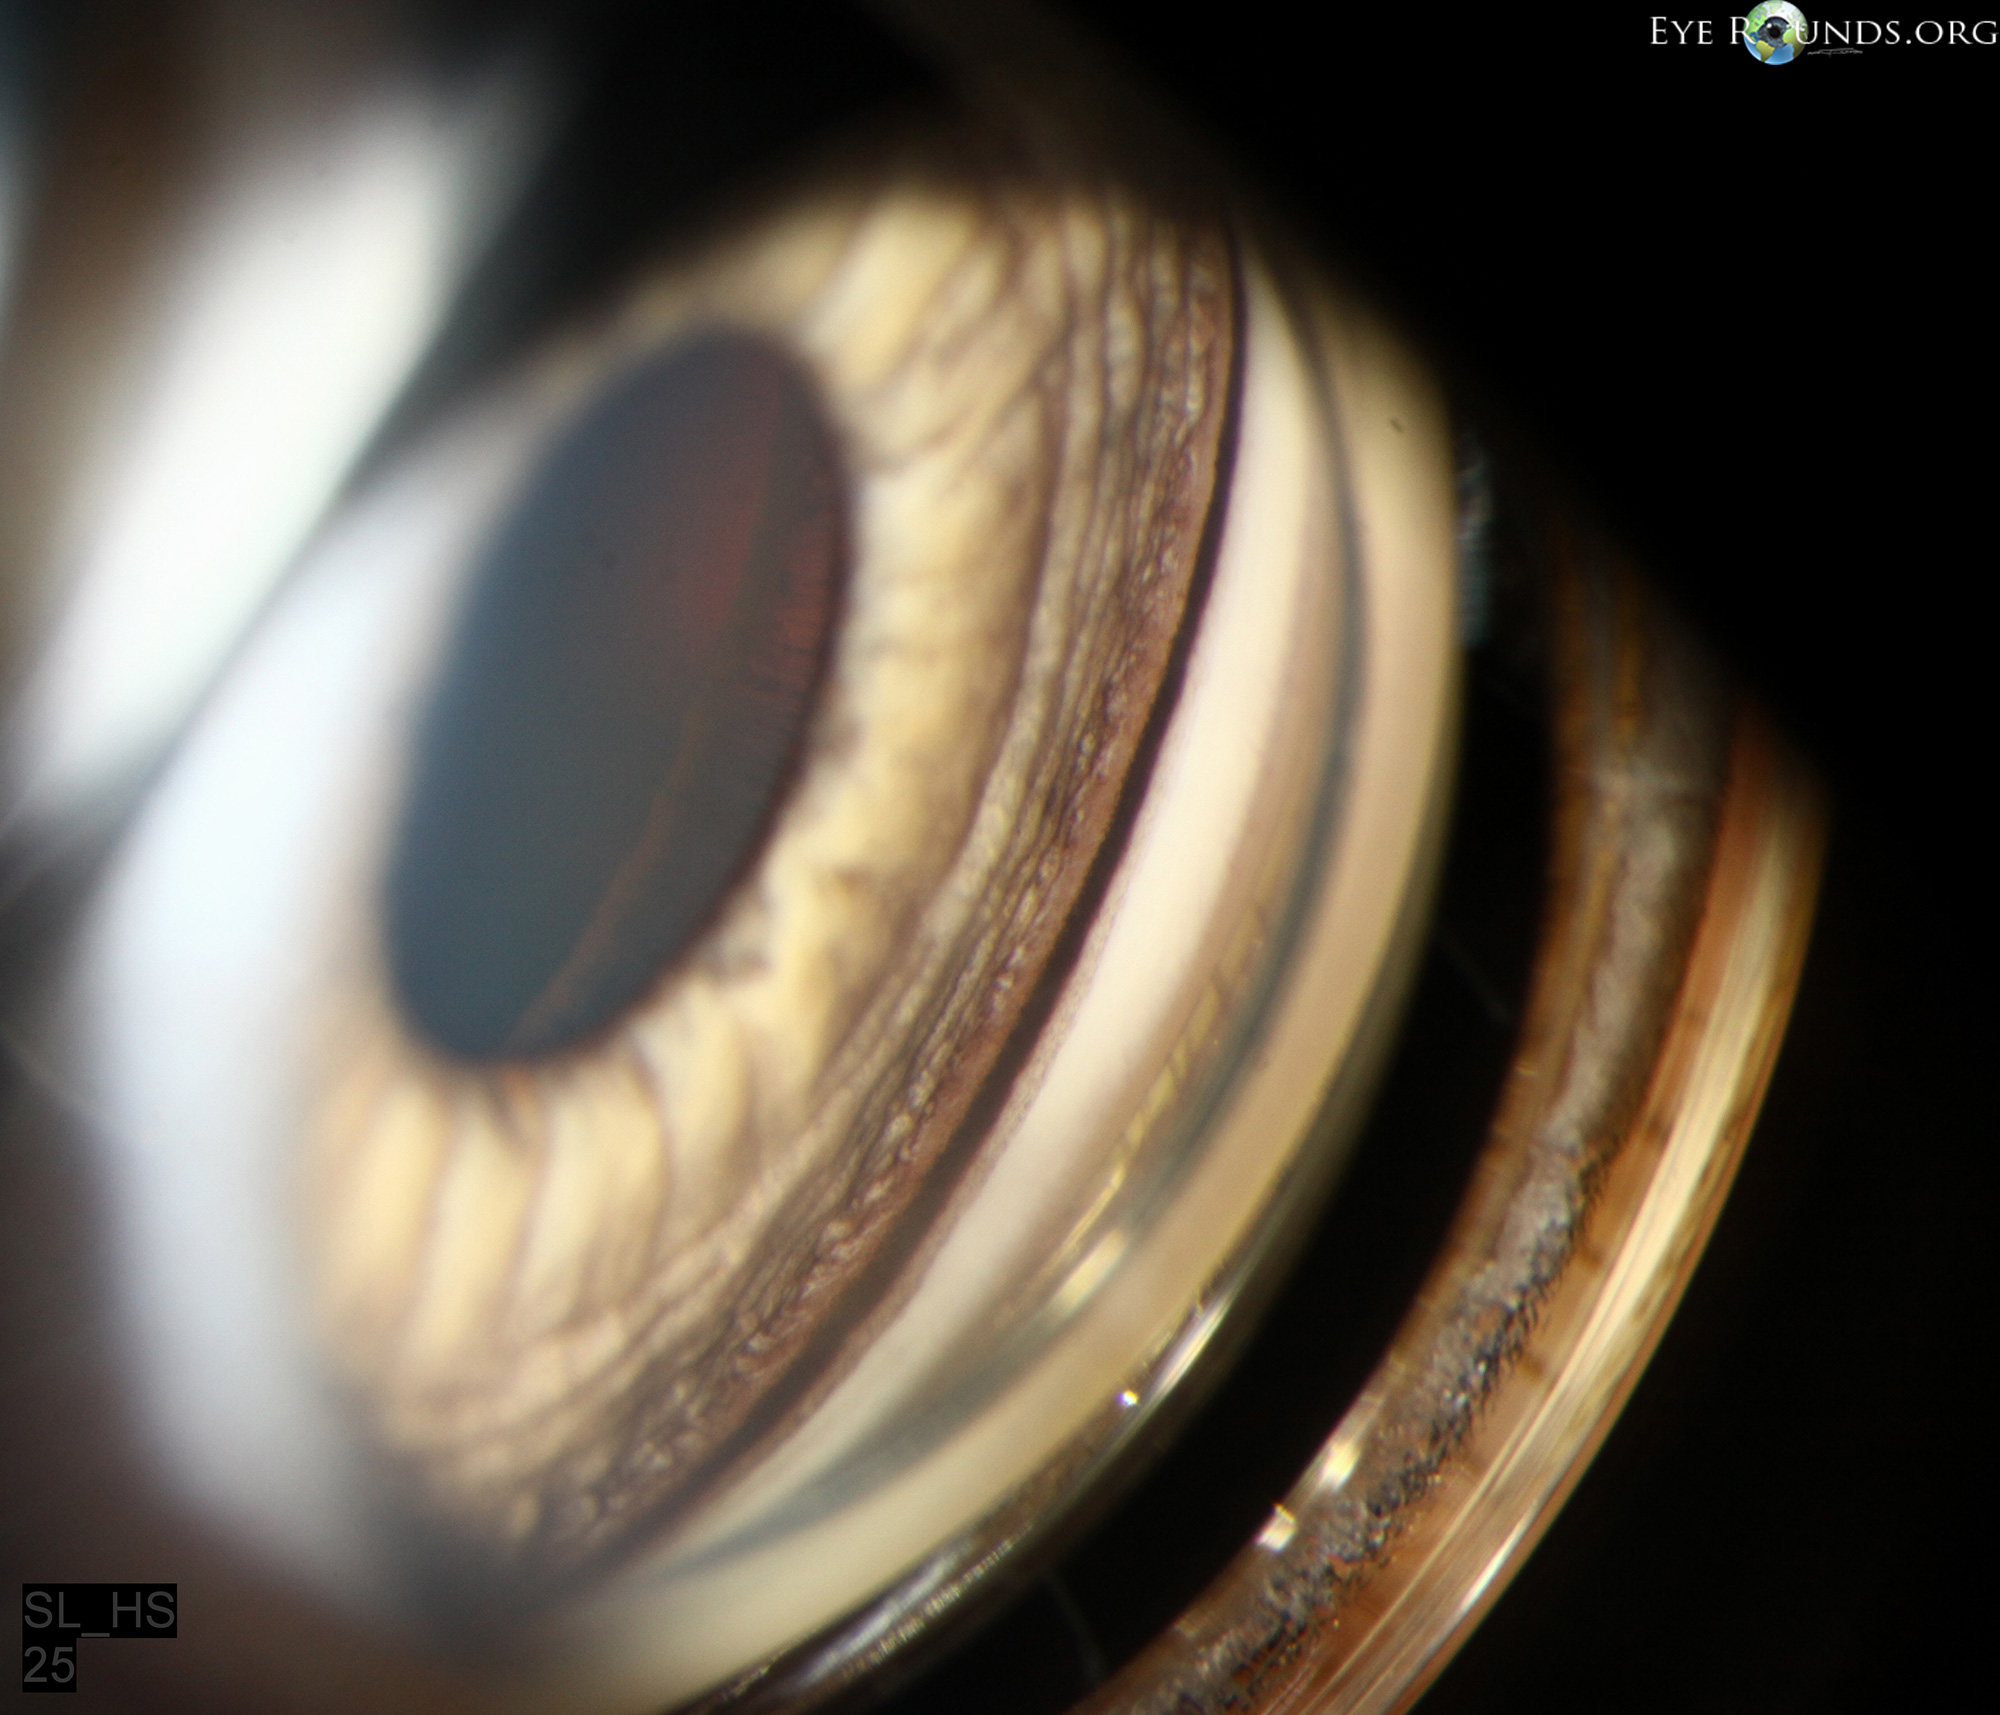

From www.eyerounds.org

Pigmentary Krukenberg's Spindle Krukenberg spindles are classically associated with primary pigment dispersion syndrome. Krukenberg spindles are an acquired form of retrocorneal pigmentation associated with intraocular pigment dispersion. Often the first sign of pds, a krukenberg spindle represents the vertical collection of pigment granules along the. Krukenberg spindle (kumar and acharya 2007). There are multiple exam findings that would indicate the presence of the. Krukenberg's Spindle.

Pigmentary Krukenberg's Spindle Krukenberg spindles are an acquired form of retrocorneal pigmentation associated with intraocular pigment dispersion. Krukenberg spindle (kumar and acharya 2007). There are multiple exam findings that would indicate the presence of the condition including a krukenberg’s spindle, sampolesi’s. Often the first sign of pds, a krukenberg spindle represents the vertical collection of pigment granules along the. Krukenberg spindles are classically. Krukenberg's Spindle.